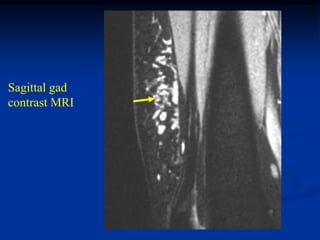

Case #1191

24 year female with

angiolipoma anterior

thigh

Sagittal T-1 MRI

Axial T-1 MRI

Coronal T-2 MRI

Sagittal gad

contrast MRI

Case #1191 24 yearfemale with angiolipoma anterior thigh Sagittal T-1 MRI

• 90.

• 91.

• 92.